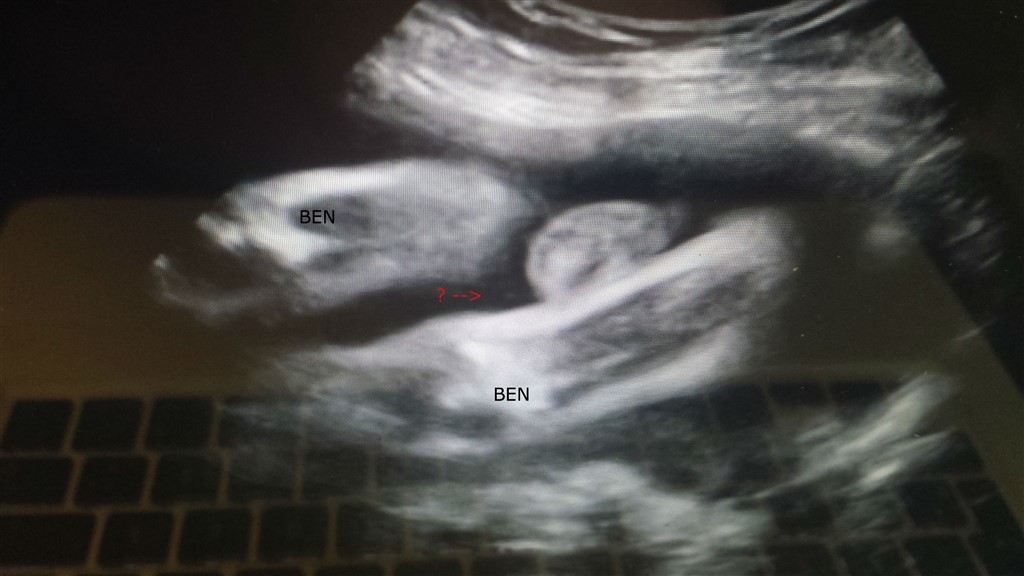

Min mand og jeg var til 3d scanning i uge 27, hvor vi fik lavet en video. Vi havde sagt vi ikke ville kende kønnet, så vi lukkede øjnene i starten af scanningen, mens lårbenet blev målt. Jordemoderen sagde dog at man tydeligt kunne se kønnet.

Nu kort inden fødslen blev vi lidt nysgerrige og fandt videoen frem. Vi er dog overhovedet ikke vant til at kigge på sådan nogle billeder, så vi synes det er svært at se, men vi har et bud

Er der nogen er jer der tør gætte?

Billederne er taget hvor baby har numsen i vejret, har prøvet at illustrere det på billederne